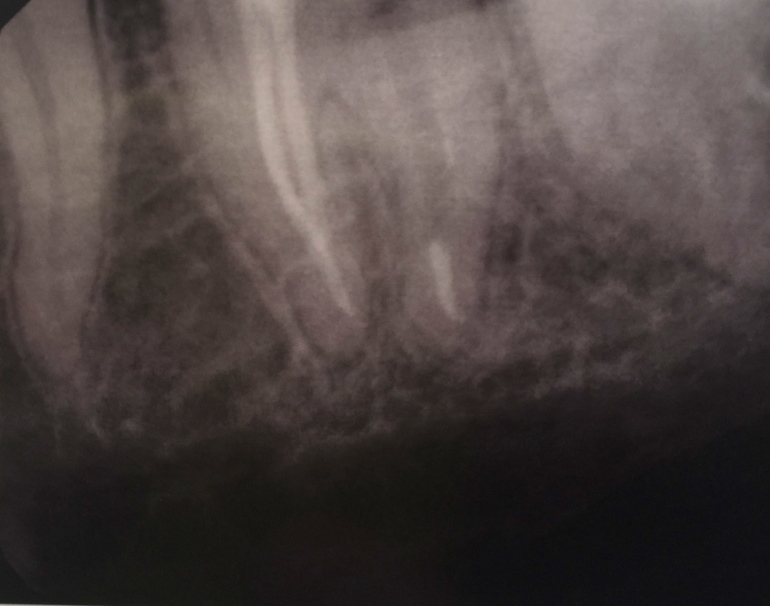

Ночью не выдержала, нашла радиовизиограф, сделала снимок, который прилагаю.